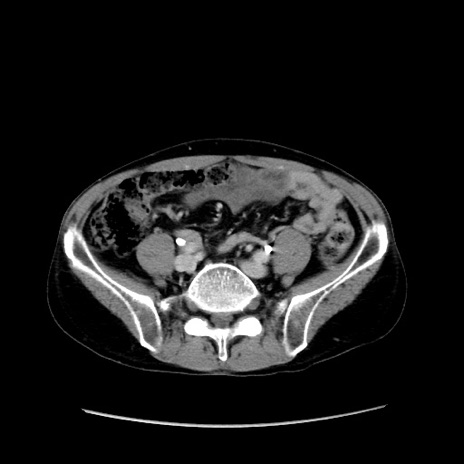

冠状断像